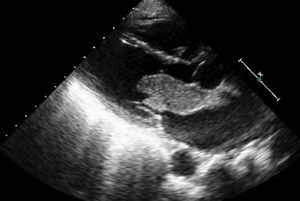

Mujer de 54años, sin factores de riesgo cardiovascular conocidos. Consultó por clínica de disnea de mínimos esfuerzos de una semana de evolución. Además refería pérdida de peso de 7-8kg en los últimos 6meses. En la exploración física se apreciaba un soplo diastólico mitral y edemas en miembros inferiores. En la analítica destacaba una anemia normocítica-normocrómica. Las enzimas cardiacas fueron negativas. Se solicitó dímeroD para descartar tromboembolismo pulmonar, que fue también negativo. El electrocardiograma mostró un ritmo sinusal a 95latidos/min. En la radiografía de tórax no existía cardiomegalia, y se apreciaban hilios congestivos y un patrón intersticial en ambas bases. En el ecocardiograma transtorácico (figs. 1 y 2) se objetivó a nivel de aurícula izquierda una masa homogénea de 47×27mm, móvil y pediculada, con pedículo adherido a tabique interauricular, que prolapsaba hacia la válvula mitral en diástole y provocaba una obstrucción intermitente de la misma, originando una estenosis mitral severa. Con la sospecha de mixoma auricular, se remitió a la paciente de manera urgente al servicio de cirugía cardiaca para extirpación de la masa. A través de una auriculotomía izquierda por vía transeptal superior se procedió a la exéresis del tumor con cauterización de la base de implantación. La anatomía patológica confirmó el diagnóstico de mixoma. La evolución posterior de la paciente fue satisfactoria, siendo dada de alta a los 7días de la intervención. En la revisión a los 6meses la paciente se encuentra asintomática.

La ecocardiografía juega un papel fundamental para poder realizar un diagnóstico precoz en estos pacientes. Nos permite descartar otras entidades que cursan con disnea y soplo, como la miocardiopatía hipertrófica y las valvulopatías. Es importante hacer el diagnóstico diferencial con los trombos intracardiacos, dado la diferente estrategia terapéutica en ambos casos. Como regla general, los trombos suelen aparecer en pacientes con fibrilación auricular, aurícula izquierda dilatada, estenosis o prótesis mitral y tricuspídea, situación de bajo gasto cardiaco y presencia de ecocontraste espontáneo en aurícula izquierda4.